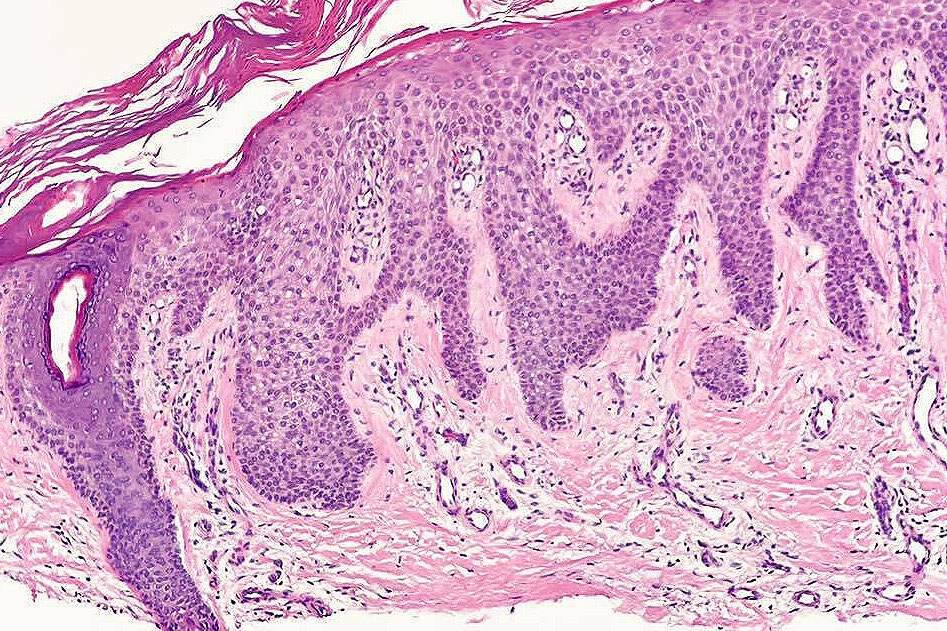

•Sharply demarcated acanthosis/psoriasiform hyperplasia; bland epithelium

•Fusion of rete ridges

•Cytoplasmic pallor or clear cell change; spongiosis sometimes present

•Characteristic intraepidermal adnexal epithelial sparing